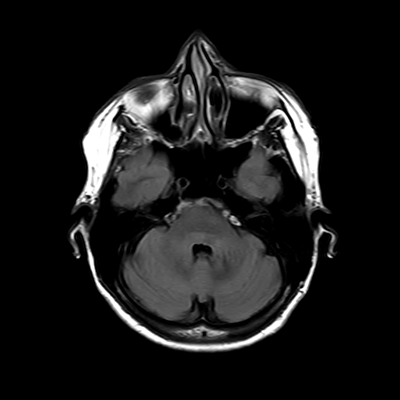

MRI brain (FLAIR)

3/18